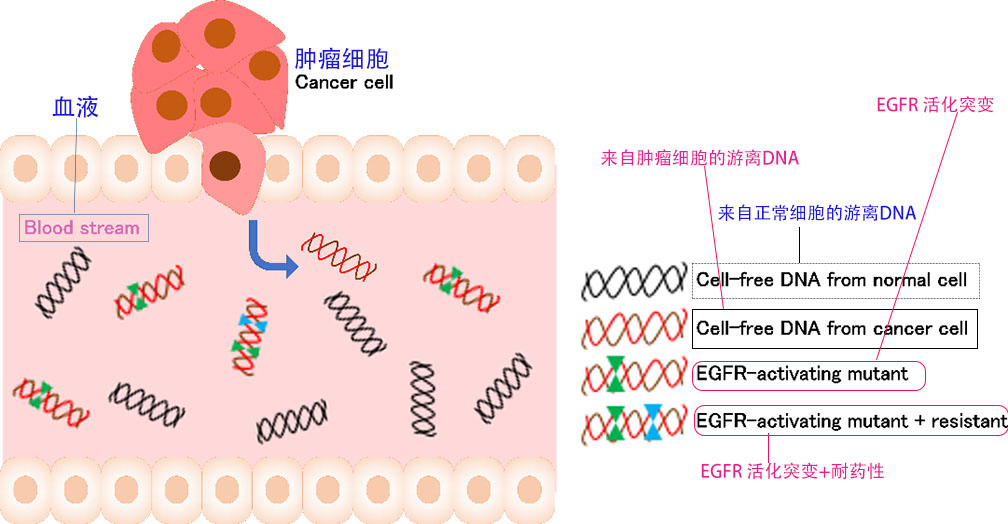

1.EGFR(表皮生长因子受体),约10%的非小细胞肺癌患者中,EGFR基因会发生异常或突变。EGFR突变可能影响肿瘤对特定药物的敏感性。(可参肺癌11基因检测)